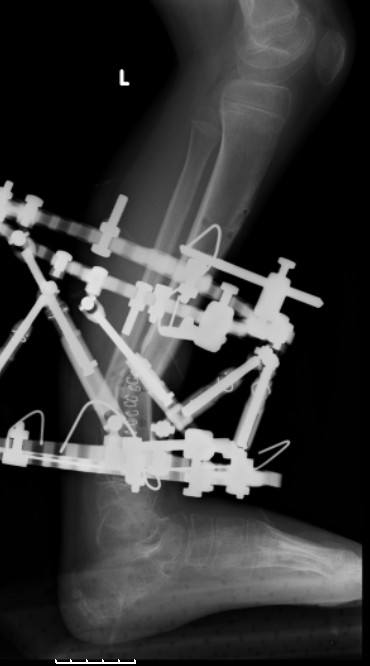

Another choice is simply perform shortening + posterior angulation with Ilizarov or TSF , than gradual correction of the angulation.After all apply third ring on the proximal tibia and start lengthening.

Another advantage of this techniqe is relaxation of soft tissue and possibility for closure even large defects of the skin.In your case I will apply ring on the foot and mid diaphysis of the tibia ,removal of the fibular plate,sindesmotic wire, and after correction of angulation on the proximal tibia.

> will apply ring on the foot and mid diaphysis of the tibia ,removal of

> the fibular plate,sindesmotic wire, and after correction of angulation

Да, надо удалить все железо, сделать для ангуляции остеотомию малоберцовой на уровне дефеормации, а после восстановления оси сразу освободить стопу. То есть в дистальном отломке tibia надо побольше

спиц с упорами, а на диафизе только half-pins с передне-внутренней стороны, чтобы как можно меньше пострадала передняя группа мышц.

Temporary Intentional Leg Shortening and Deformation to Facilitate Wound Closure Using the Ilizarov/Taylor Spatial Frame Shane J. Nho, MD, David L. Helfet, MD, and S. Robert Rozbruch, MD (PDF, 474 Kb)